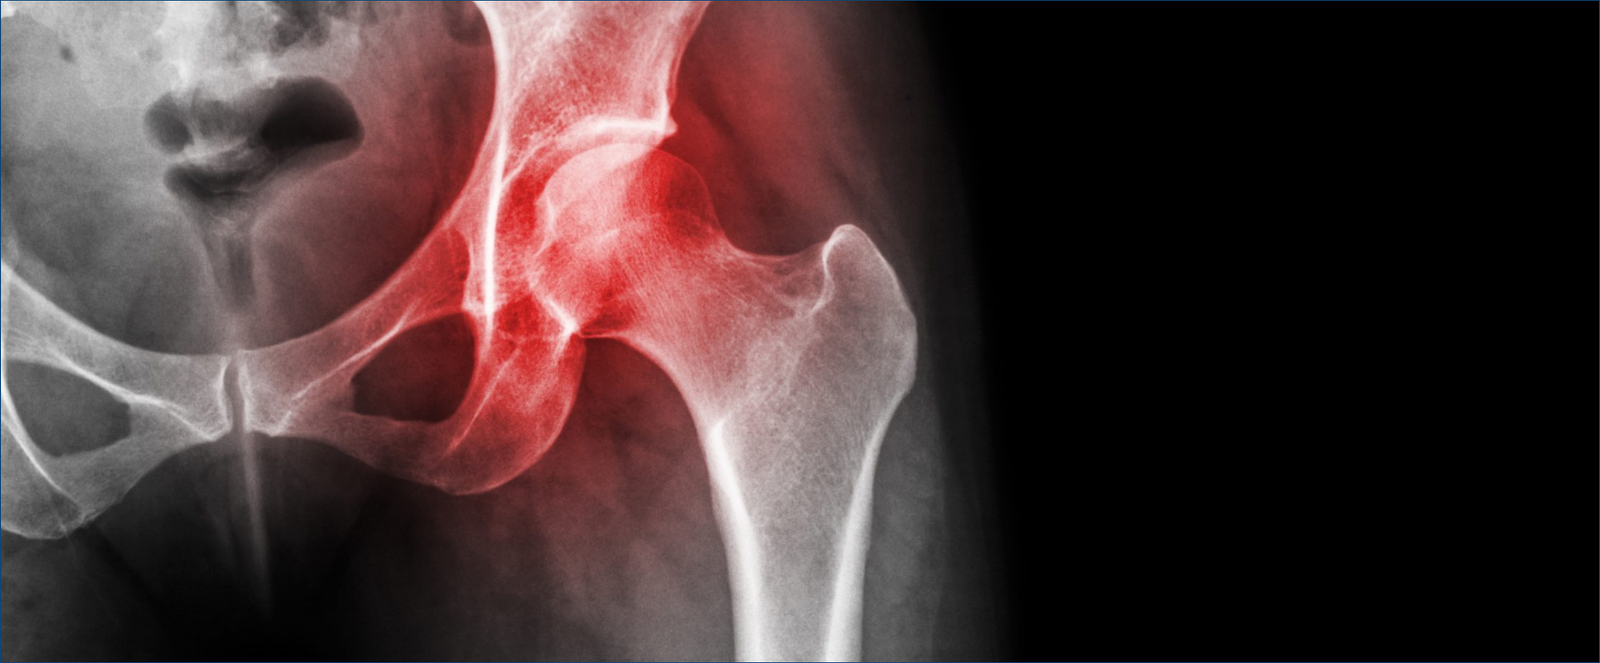

Avascular necrosis

Avascular necrosis (AVN) is a condition that occurs when the blood supply to the bone is disrupted, leading to bone death. This can occur in any bone, but it is most common in the hip joint.